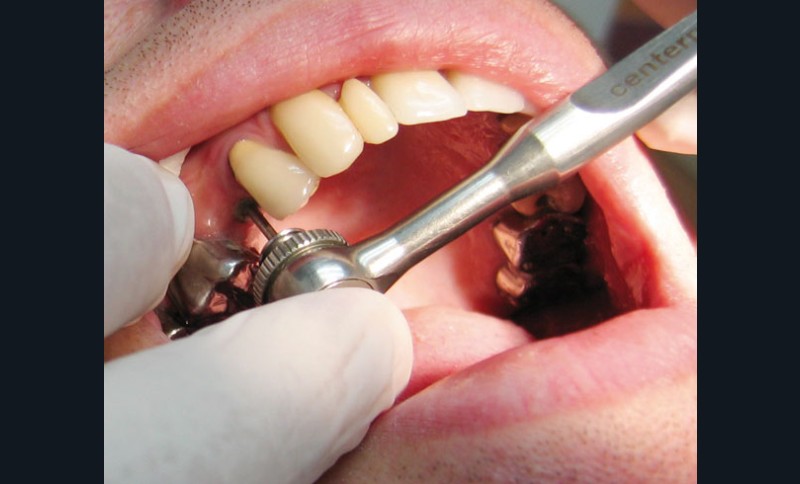

Puis le tournevis est calé sur l’embout (fig. 6) et la vis est retirée (fig. 7).